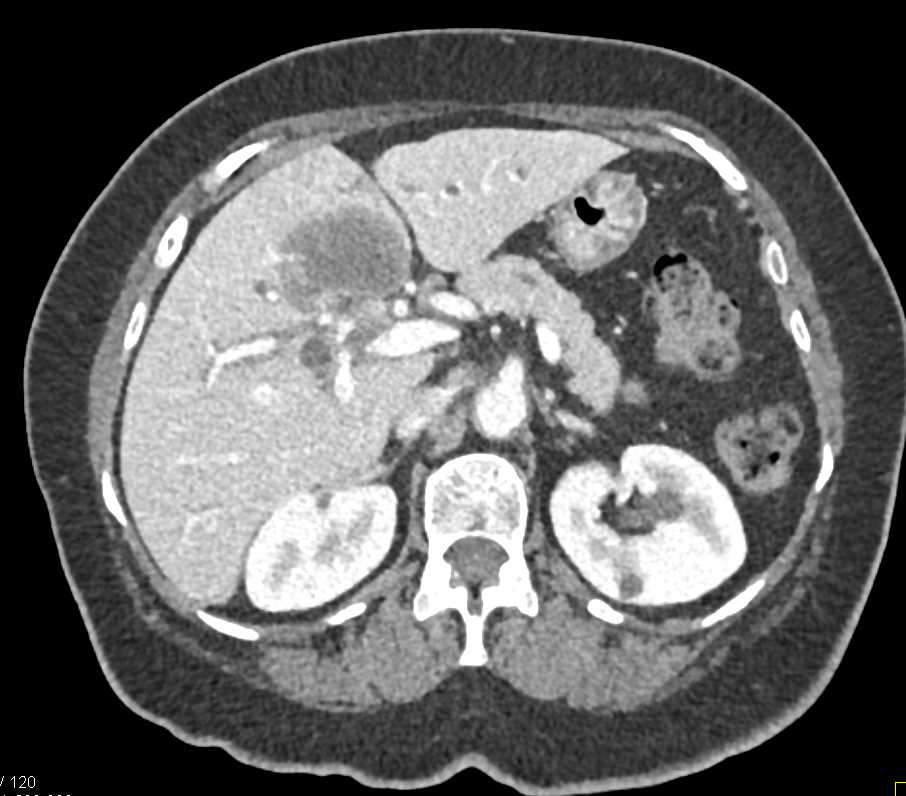

Focal Fat Simulates and Adrenal Lesion